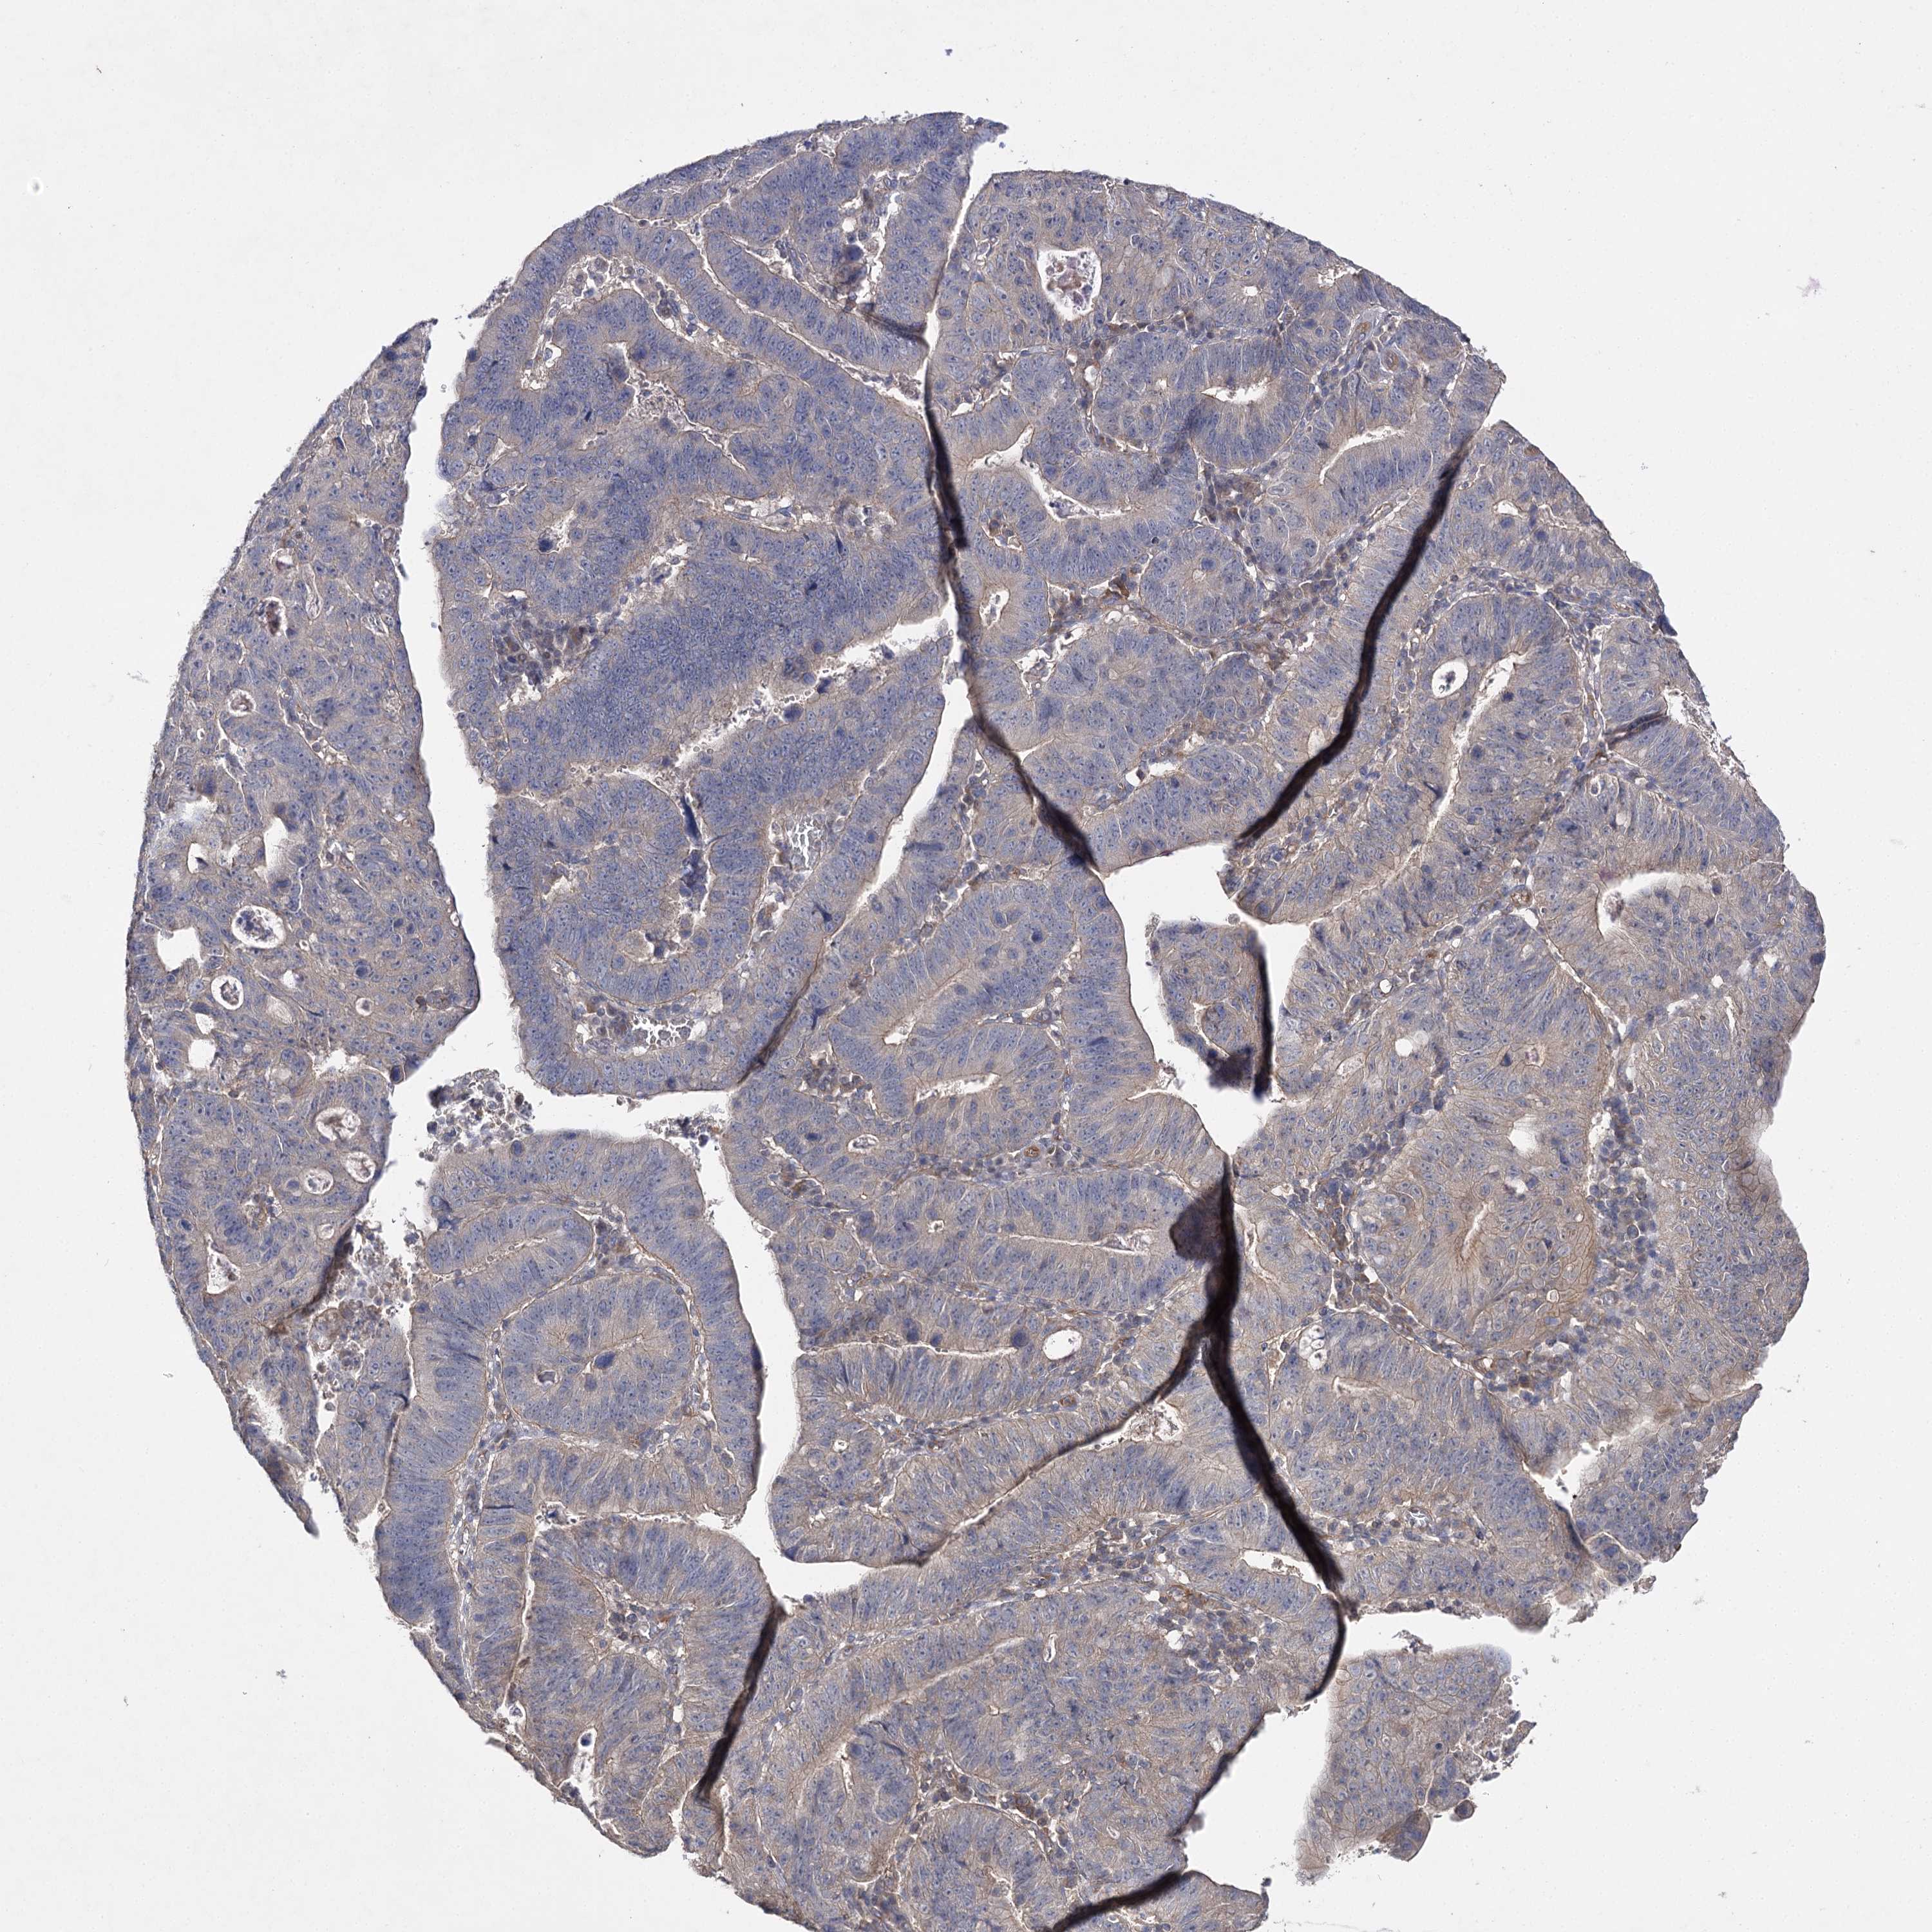

STOMACH CANCER - Protein expressioni

A mouse-over function shows sample information and annotation data. Click on an image to view it in a full screen mode. Samples can be filtered based on level of antibody staining by selecting one or several of the following categories: high, medium, low and not detected. The assay and annotation is described here.

Note that samples used for immunohistochemistry by the Human Protein Atlas do not correspond to samples in the TCGA dataset.

Antibody stainingi

Antibody staining in the annotated cell types in the current human tissue is reported as not detected, low, medium, or high, based on conventional immunohistochemistry profiling in selected tissues. This score is based on the combination of the staining intensity and fraction of stained cells.

Each image is clickable and will lead to virtual microscopy that enables deeper exploration of all samples and also displays staining intensity scores, fraction scores and subcellular localization as well as patient and tissue information for each sample.

Antibody HPA038337

Antibody CAB010421

Antibody CAB018545

Staining

Adenocarcinoma, NOS